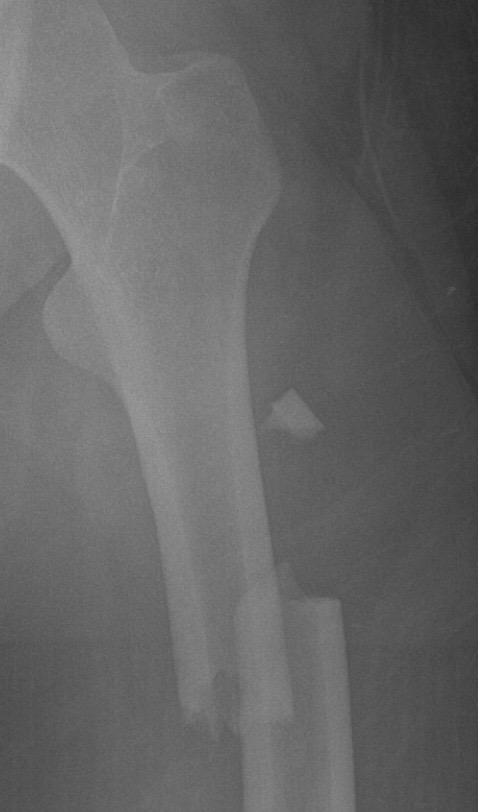

On January 29th Lily’s car lost control after hitting an icy patch on the way to work. Her car flipped and hit a tree. She sustained multiple injuries in her spine, a broken femur (left leg) and humerus (right arm), as well as suffering from a collapsed lung. She was in trauma care for over 2 weeks and will be moved to a physical therapy rehab until she learns to walk again. She is unable to take care of herself at the moment and won’t be able to return to work anytime soon.